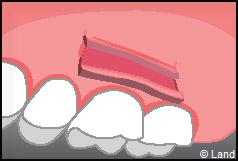

Les greffes de conjonctifs enfouis :

Destinées aux zones esthétiques, elles consistent à prélever la partie profonde du palais (site donneur).

Ce greffon est ensuite inséré sous la gencive au niveau de la récession (site receveur).